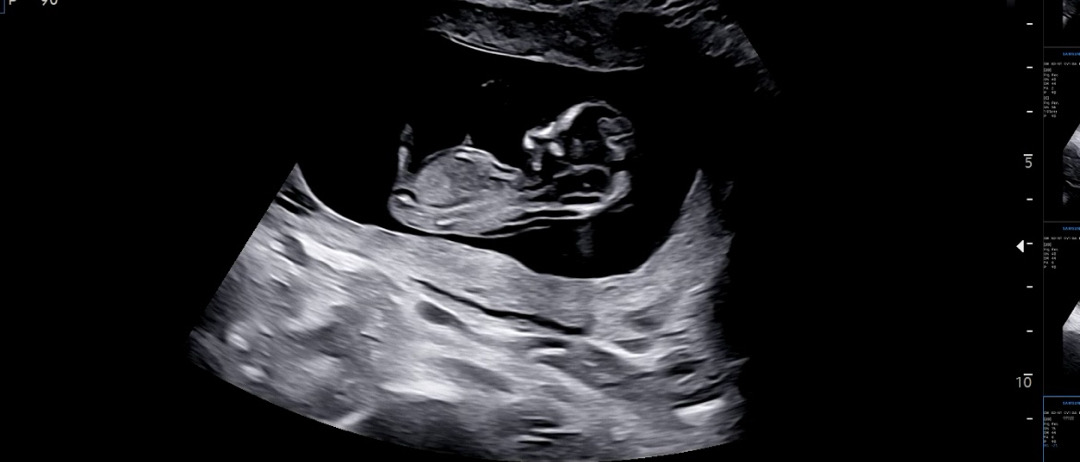

12주1일차 각도법 봐주세요 🙂

어떤건 올라갓고 어떤건 평행한거같고.. 사진이 여러장이 안올라가네요 ㅠㅠ